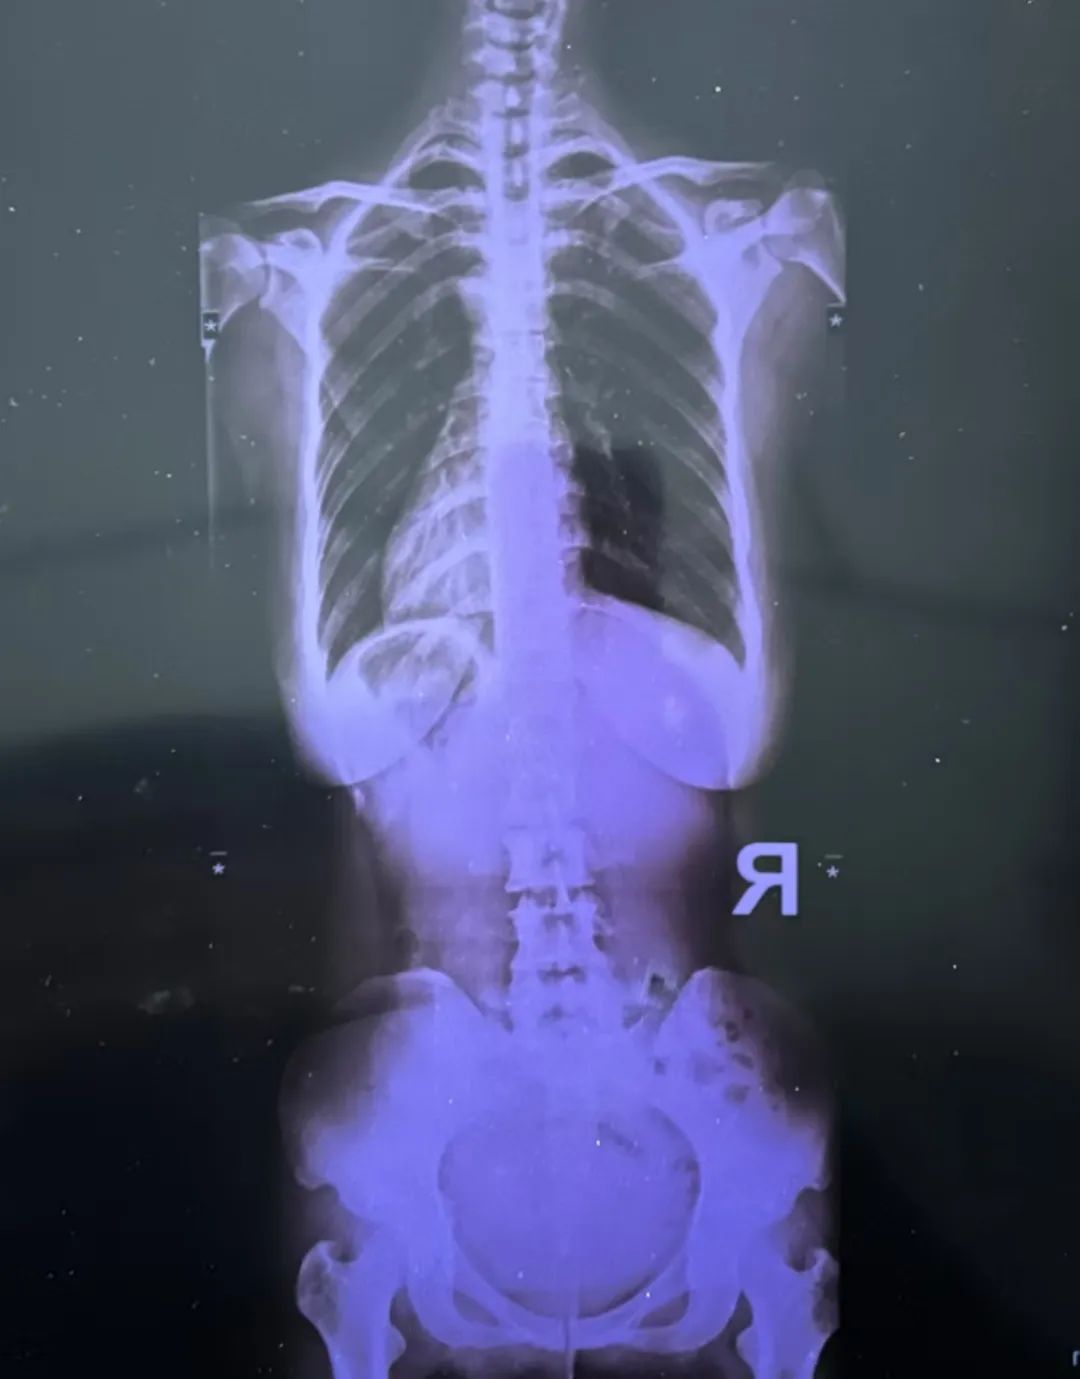

最近又疼起來嚴(yán)重影響正常生活,她前往醫(yī)院就診,結(jié)果查出了脊柱側(cè)彎11°,骨盆旋移,骶髂關(guān)節(jié)半脫位,由于這些導(dǎo)致頸肩,后背,腰部肌群代償出現(xiàn)問題,從而出現(xiàn)腰痛,后背痛,肩膀痛!

蘇鴻凱醫(yī)生根據(jù)王女士的具體情況,為王女士制定針對(duì)性治療方案,在治療中采用正骨手法復(fù)位,在配合結(jié)構(gòu)針法治療,來調(diào)節(jié)肌肉功能使恢復(fù)平衡。